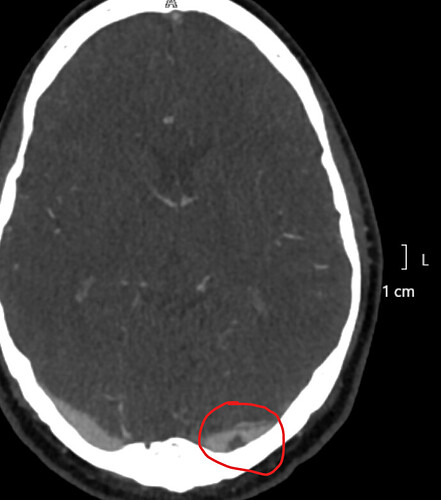

The arachnoid granulations are in the veins at the back of the head. They call those sinuses, too, just to confuse everyone. ![]()